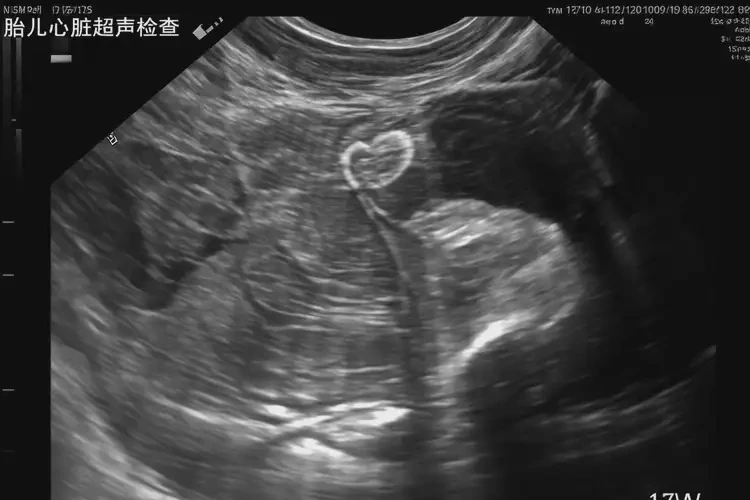

懷孕11周胎心80怎么回事(圖2)

• 胎兒心臟超聲:可以詳細(xì)評估胎兒心臟結(jié)構(gòu)和功能,確定是否存在心臟畸形或其他異常。

• 胎盤超聲:可以評估胎盤位置、形態(tài)和功能,確定是否存在胎盤早剝或前置胎盤等問題。